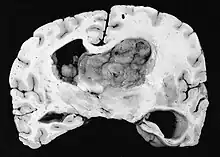

Subependymal giant cell astrocytoma (SEGA, SGCA, or SGCT) is a low-grade astrocytic brain tumor (astrocytoma) that arises within the ventricles of the brain.[1] It is most commonly associated with tuberous sclerosis complex (TSC). Although it is a low-grade tumor, its location can potentially obstruct the ventricles and lead to hydrocephalus.

Diagnosis

a,b)Images of subependymal giant cell astrocytomas arrowheads -

MRI of brain with sub-ependymal giant cell astrocytoma

Diagnosis is made by imaging with a contrast-enhanced MRI or CT scan of the brain.[3]